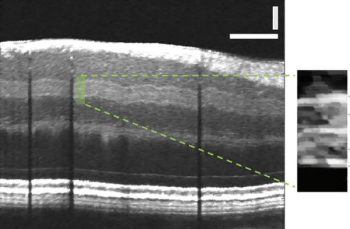

Tibor Juhasz, CEO of ViaLase, Inc, discusses the company's development of a novel, noninvasive high-resolution OCT image-guided femtosecond laser technology for the treatment of open-angle glaucoma.